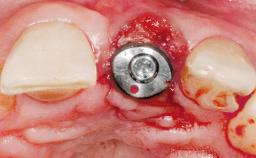

Immediate Flapless Placement of an Implant in a Maxillary Right Lateral Incisor Site

This 43-year-old male patient, a non-smoker, came to our practice because of a fracture of tooth 12 caused by a bicycle accident. Due to the combined para- and infrabony crown and root fracture, tooth extraction, and subsequent implant placement were suggested to the patient as the therapy of choice. The patient had high esthetic expectations with regard to the treatment outcome and asked for an immediate fixed provisional restoration. His individual esthetic risk profile summed up to a medium esthetic risk.

Placement Protocol Immediate implant placement

Loading Protocol Immediate

Provisional Implant-Supported Prosthesis Prosthodontic margin > 3 mm apical to mucosal margin Prosthodontic margin > 3 mm apical to mucosal margin